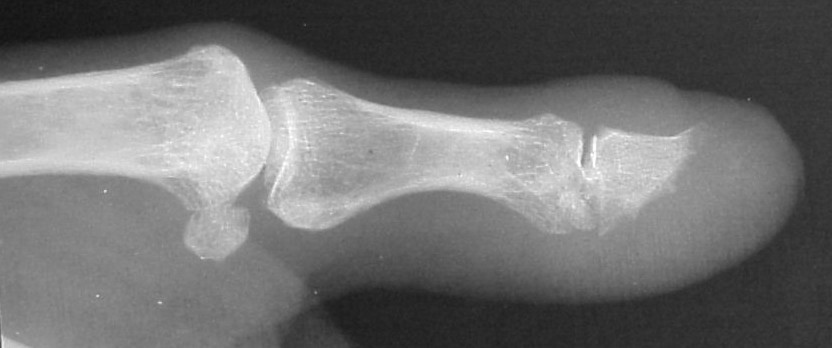

Plain films showed resorption of the distal two thirds of the distal phalanx:

Comparison views of the opposite side: